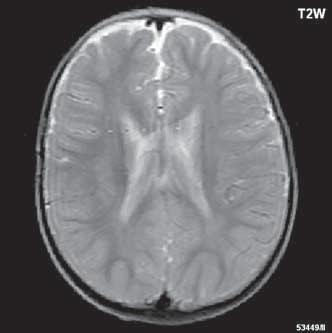

Obr. I.1.1h Fyziologický nález, již normální šíře subarachnoidálních prostor (věk 1,5 roku); stejný pacient jako na obr I 1 1f, g

Obr. I.1.1ch Fyziologický nález, již normální šíře subarachnoidálních prostor (věk 1,5 roku); stejný pacient jako na obr I 1 1f, g, h